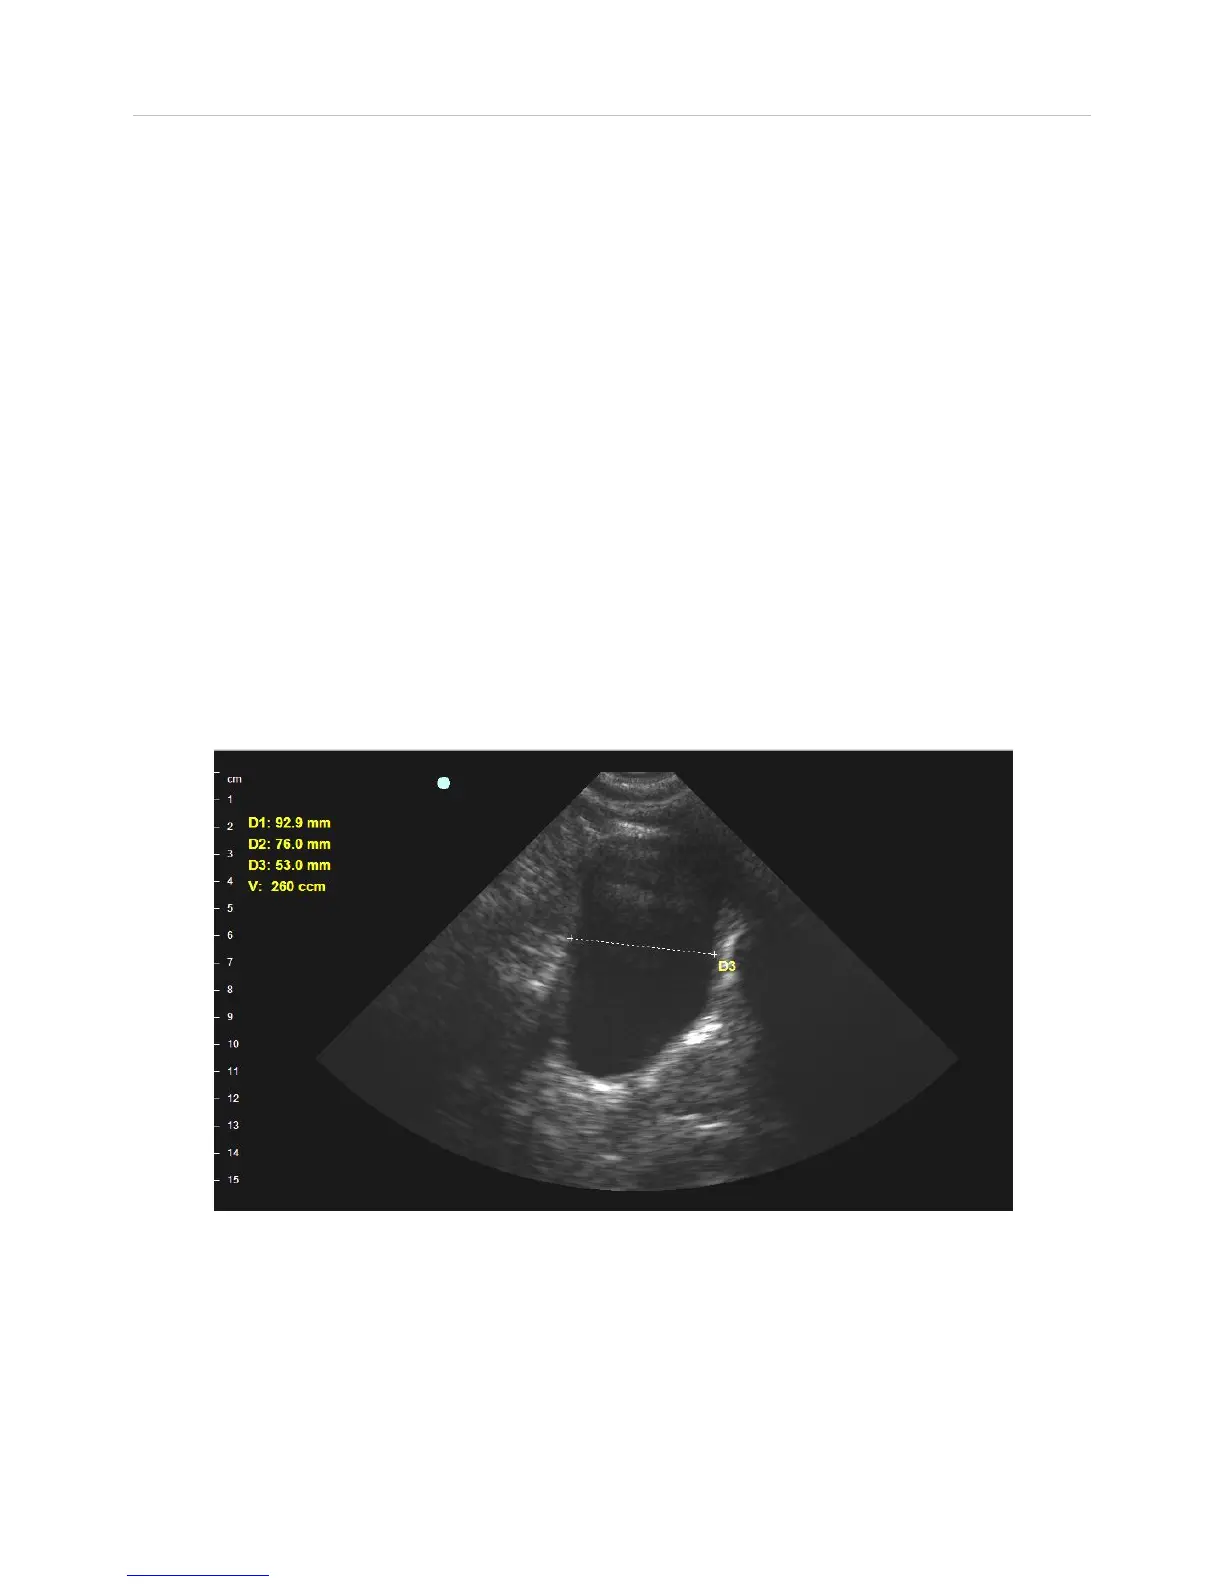

ViewBladder 10

Quick Start Guide

5. Freeze the image by pressing the blue button on the probe or the yellow

pause Scan button on the screen.

6. After freezing the image, measure the height of the displayed bladder by

placing your finger on one edge of the bladder and swiping to the opposite

side. Similarly measure the width. If you feel you did not optimally place

your finger, double tap to remove the current measurement and then swipe

your finger again.

7. Follow the onscreen prompts, displayed in yellow beneath the patient exam

box to take the mid-sagittal scan. By rotating the probe 90 degrees you will

be viewing the thickness of the bladder. Start the scan and then freeze

when you have the optimal bladder image.

9. Measure the thickness of the bladder by placing your finger on the edge of

the bladder and swiping to the opposite side. The mid-sagittal bladder

image is often displayed at a slight angle, either up or down. Therefore, to

make the most accurate measurement, always measure the thickness at the

appropriate angle.

10. ViewBladder 10 will calculate and display the bladder volume. If you find

you did not optimally place your finger, double tap to remove the volume

calculation and the D3 measurement. Repeat the D3 measurement.